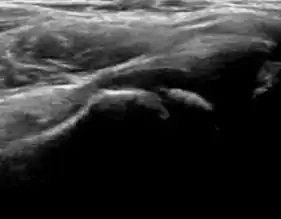

A step between the head and the physis can be detected in children with SCFE, while abnormalities in the femoral head contour may suggest the presence of LCPD. In both cases, radiographs are mandatory to confirm diagnosis and severity (Figure 12).[1]

Figure 12:

Normal ultrasound appearance of the femoral head-neck junction.

Joint effusion in transient synovitis of the hip.

Flattening of the femoral head in a patient with Perthes disease.

Step in the femoral head-neck junction in a patient with SCFE.